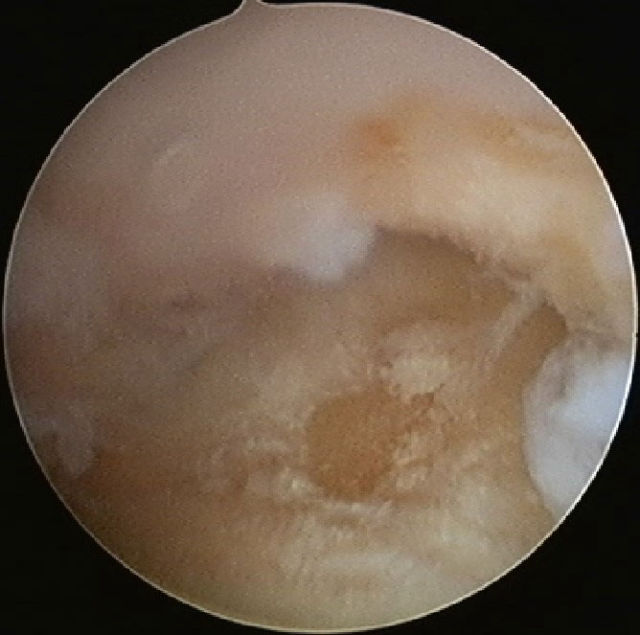

Sollte diese Injektion keine oder keine ausreichende Wirkung zeigen oder die Wirkung hält nur kurz an, dann wäre als nächster Schritt die Arthroskopie (Gelenkspiegelung) des Sattelgelenkes erforderlich.

Bei dieser relativ kleinen Operation wird eine 2,5 mm dicke Optik mit Kamera in das Sattelgelenk eingeführt. Man kann dann erkennen, inwieweit der Gelenkknorpel geschädigt ist und wie stark die entzündlichen Veränderungen ausgeprägt sind. Es kann dann mit einer kleinen Fräse oder einem sogenannten „VAPR" eine Reduktion des entzündlichen Gewebes und/oder eine Glättung des Knorpels durchgeführt werden (Gelenktoilette), gleichzeitig können Knorpelanteile, die frei im Gelenk liegen (freie Gelenkkörper) entfernt werden.

Arthroskopiebefund: Knorpelschaden am Os trapezium